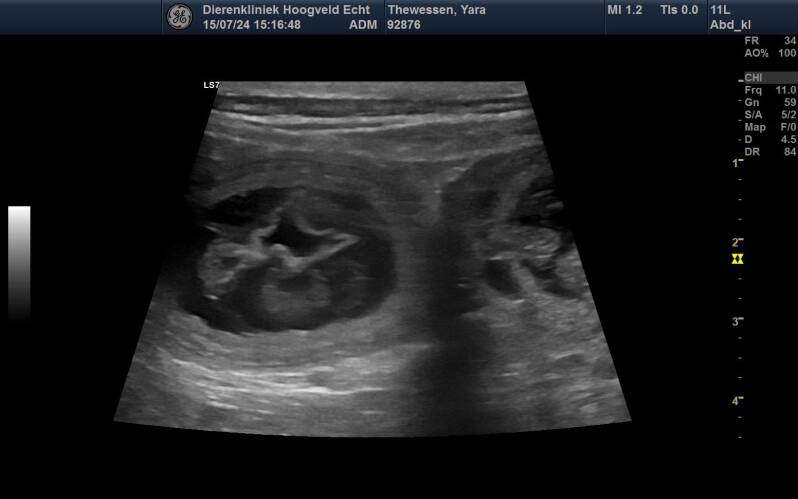

Jaaaa, ze is drachtig....

Vandaag de echo gehad, ze is zwanger!! Erg blij mee. Als alles verder goed gaat zijn er rond 19 Augustus puppies....